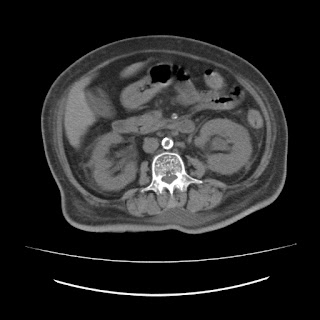

72 YEAR OLD FEMALE WITH UNCONTROLLED DIABETES

UNCONTROLLED SUGARS SECONDARY TO TYPE 2 DIABETES MELLITUS.